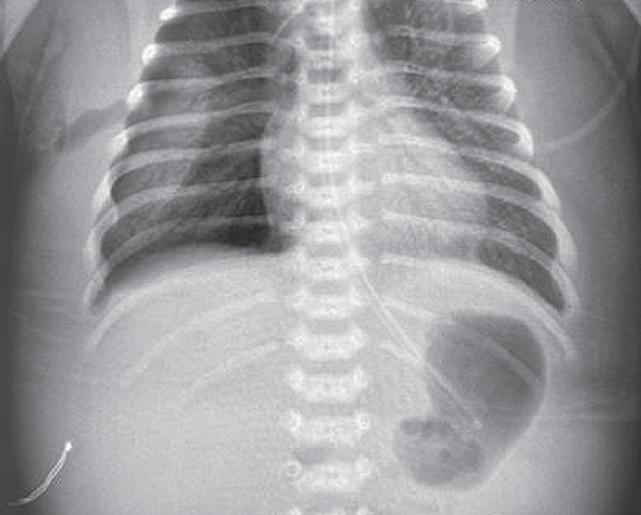

На этом фоне отмечается выраженный положительный эффект в виде увеличения SpO2 с 7–23 до 90 %, на контрольной рентгенограмме сразу после введения порактанта альфа (рис. 3) отмечается незначительное улучшение пневматизации левого легкого, сохраняется свободный воздух в правой плевральной полости.

Рис. 3. Рентгенограмма органов грудной клетки новорожденного после монобронхиального введения сурфактанта

Fig. 3. Chest X-ray of newborn after monobronchial surfactant administration